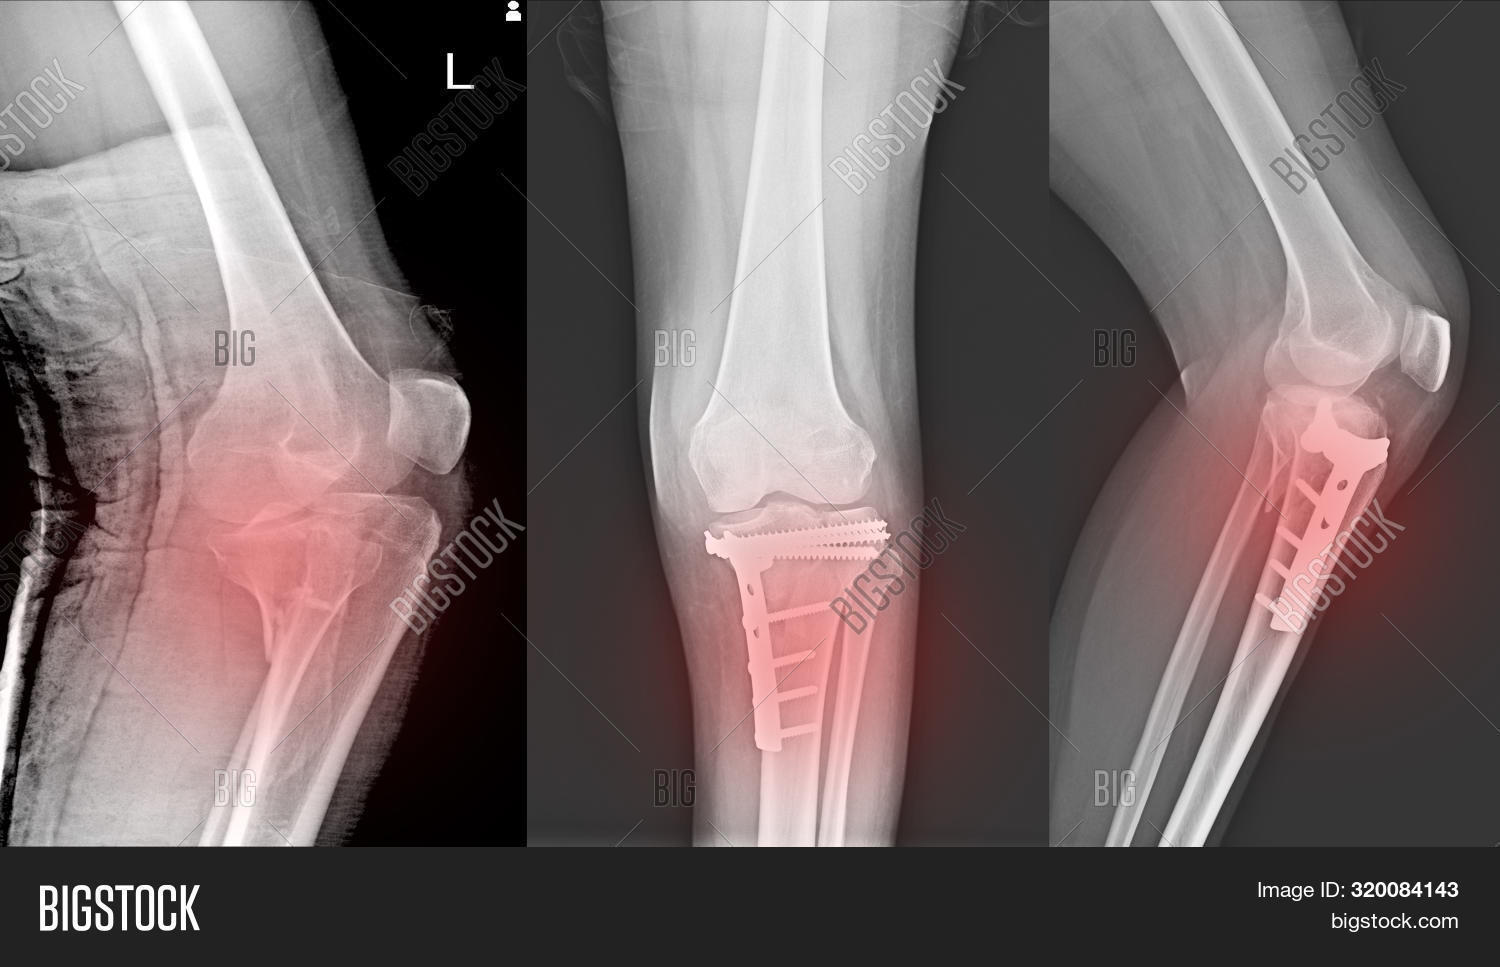

Xray Knee Joint Fracture Proximal Tibia and Post Fix Fracture Proximal Knee Joint Fracture X Ray Horizontal ray (lateromedial) = supine + knee extended. increased signal intensity, thickening, and cysts within and adjacent to acl are common findings, and clinically insignificant (no. this system divides tibial plateau fractures into six types: there are several ‘avulsion’ fractures that indicate significant joint derangement. Important examples are the segond fracture (avulsion from. Ct scans are used. Knee Joint Fracture X Ray.

Xray Knee Joint Fracture proximal tibia and Post fix fracture proximal Knee Joint Fracture X Ray this system divides tibial plateau fractures into six types: Important examples are the segond fracture (avulsion from. Horizontal ray (lateromedial) = supine + knee extended. Ct scans are used to further. increased signal intensity, thickening, and cysts within and adjacent to acl are common findings, and clinically insignificant (no. there are several ‘avulsion’ fractures that indicate significant. Knee Joint Fracture X Ray.

Xray Knee Joint Fracture proximal tibia and Post fix fracture proximal Knee Joint Fracture X Ray this system divides tibial plateau fractures into six types: Horizontal ray (lateromedial) = supine + knee extended. increased signal intensity, thickening, and cysts within and adjacent to acl are common findings, and clinically insignificant (no. there are several ‘avulsion’ fractures that indicate significant joint derangement. Important examples are the segond fracture (avulsion from. Ct scans are used. Knee Joint Fracture X Ray.